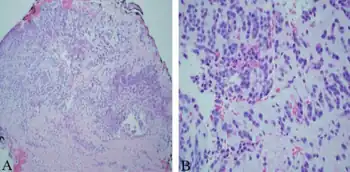

| a,b)Monomorphic round tumor cells with minimal cytoplasm in loose myxoid background, consistent with extraskeletal myxoid chondrosarcoma. | |

EMC shows the smallest morphological variation between the tumors among all myxoid soft tissue neoplasms. The myxoid matrix has a fibrous structure that is different from the grainy appearance of most other myxoid lesions. It is stained with magenta in the air-dried samples. Among all myxoid tumors, EMC has the least vascular structures. Chondroblast-like lacunas may be formed, but no differentiation of hyaline cartilago has been described.

Smears contain plump spindle-shaped or oval tumor cells arranged in a lacelike pattern of loosely cohesive cords and nests. The malignant cells are uniform and lack nuclear pleomorphism. The nuclei have round or oval shape and are hyperchromatic with finely stippled chromatin. The nucleolus is small and inconspicuous. Nuclear clefts and grooves are common and the cytoplasm is homogeneous, scanty to moderately abundant, and often appears wispy and tapered, with well-defined borders of cells.